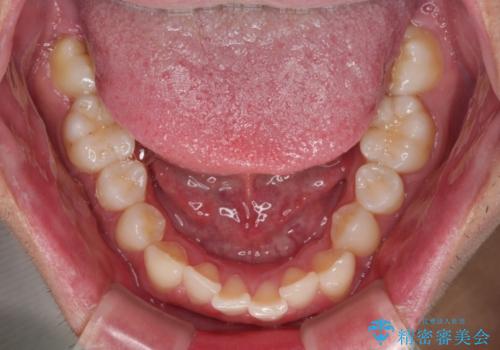

- ディープバイトと上顎前歯の突出、奥歯の咬み合わせを気にして来院された患者様です。

上顎歯列は全体的に前方位にあり、それが原因で深い咬み合わせとなり、突き上げにより上顎前歯が前方に飛び出している状態でした。

また、左右ともに上顎最後臼歯が頬側に転位している鋏状咬合となっていました。

インビザラインによる矯正治療をご希望でしたが、上顎歯列の前方位と鋏状咬合を確実に改善することを目的として、補助装置を併用することとしました。